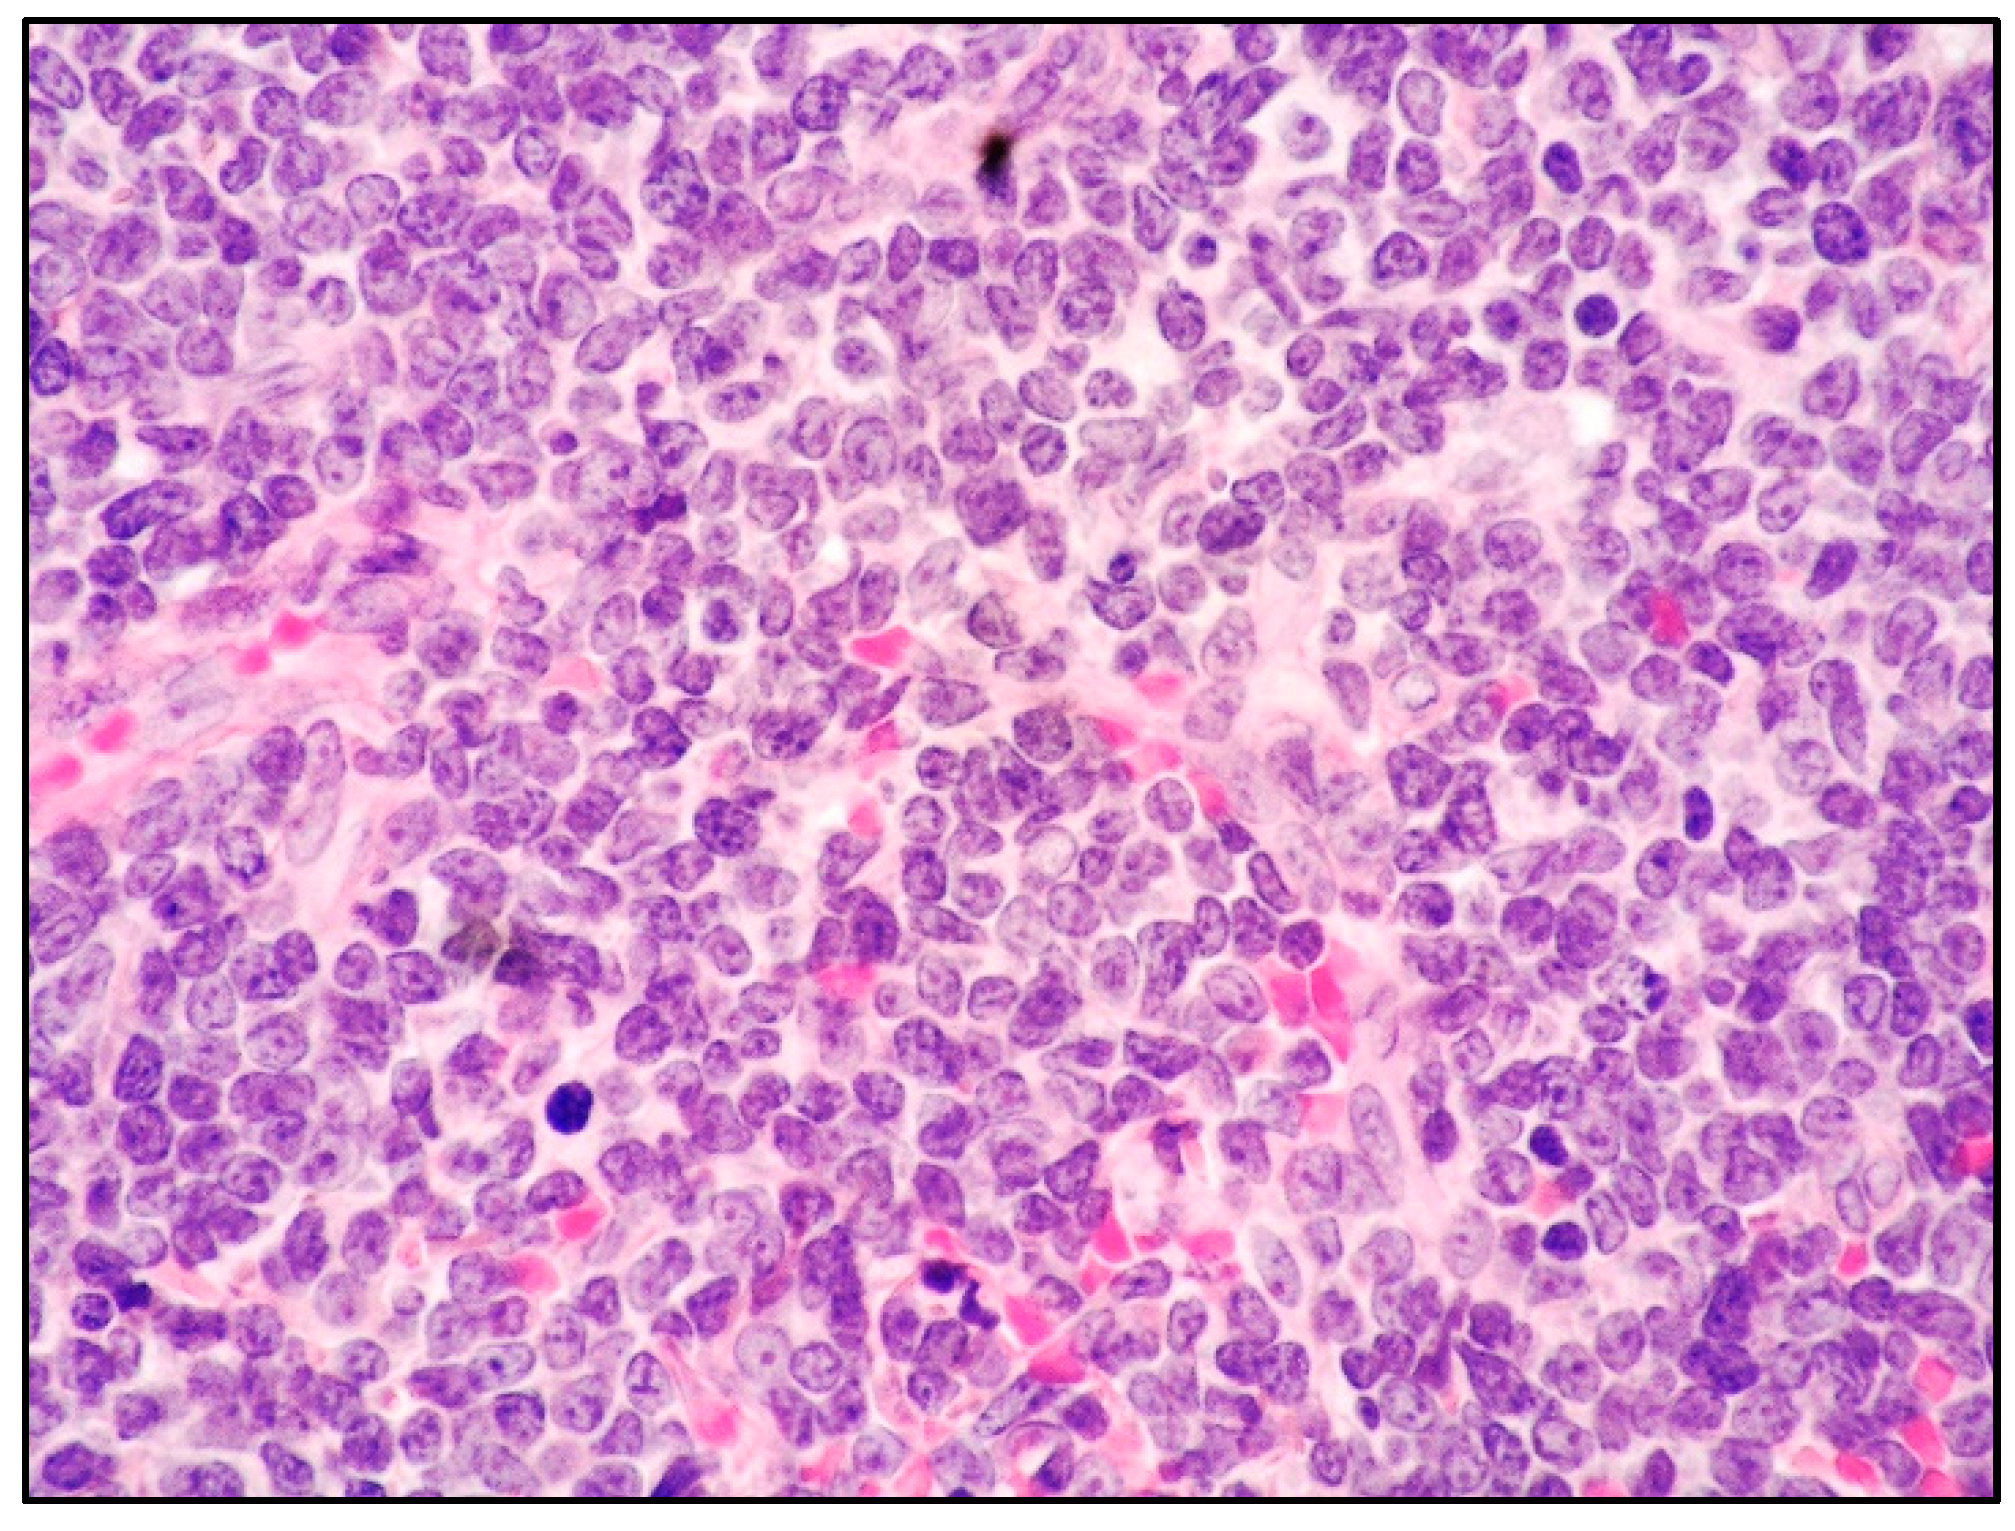

7. Histology and Immunophenotypic Features of B-LBL and T-LBL

8. LBL and Skin Involvement